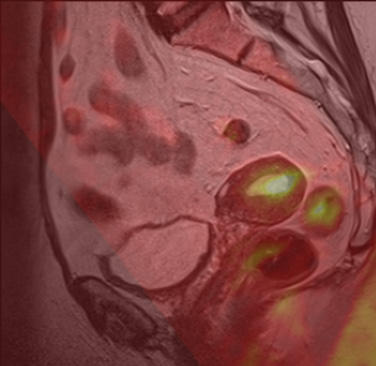

Functional imaging for individualised cancer treatment (Professor Ingfrid Haldorsen).

The research group aims to:

- Explore functional imaging findings i.e. potential imaging biomarkers that predict advanced tumor stage, lymph node metastases and reduced survival in patients with uterine cancers.

- Validate and compare these imaging biomarkers with established histomorphological and molecular biomarkers in uterine cancers.

- Implement these imaging biomarkers in the preoperative risk stratification to enable better tailored and individualized treatment of uterine cancers.

- Explore functional imaging findings in an orthotopic animal model of primary and metastatic lesions of uterine cancers.

- Explore imaging characteristics as tools to detect early drug response in orthotopic tumour grafts.